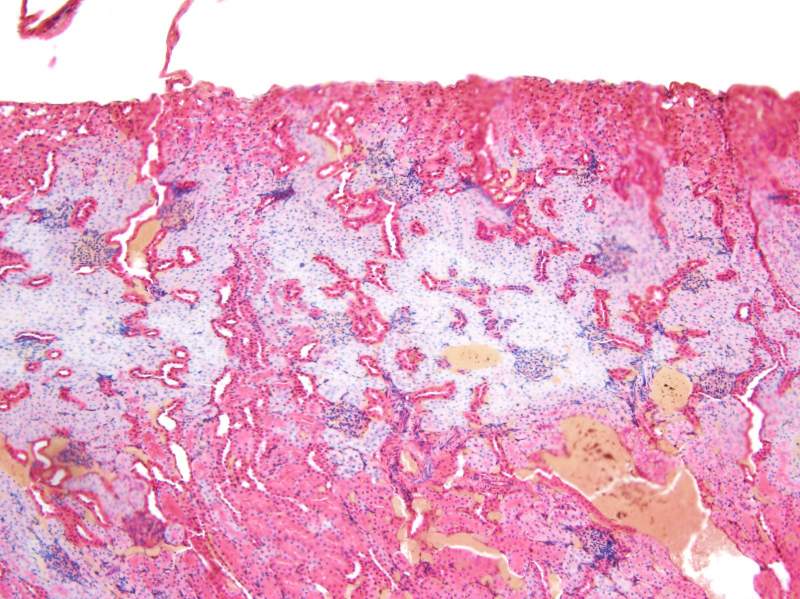

求助肾脏HE染色问题,急求 已有1人参与